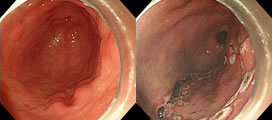

내시경 시행 중 용종이 발견되었을 경우 작은 용종은 겸자를 이용해서 단순 제거를 하게되고, 5mm 이상의 용종은 크기에 따라 점막 절제술 (Endoscopic Mucosal Resection, EMR) 혹은 용종 절제술 (Hot Snare Resection)을 시행하게 됩니다. 점막하층에 용액을 주입하여 병변을 융기시킨 후 올가미(snare) 등을 이용하여 절제술을 시행하게 됩니다.

상부 내시경, 대장 내시경에서 2cm 이상의 큰 병변이나, 종양성 병변이 발견될 때에는 내시경적 점막하 박리절제술 (Endoscopic Submucosal Dissection, ESD)을 시행할 수 있습니다. 본원에서는 위장, 대장의 점막하 박리절제술이 모두 가능합니다.